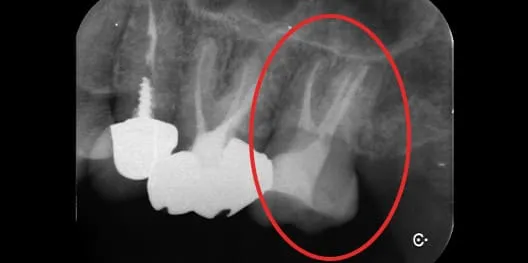

治療前 治療前

治療後 治療後

感染根管治療の症例

主訴

左上の歯ぐきが腫れている

治療内容

感染根管治療

患者さまの年齢

64歳

治療期間

2週間(治療回数は2回)

治療費用

¥132,000+再診料¥3,300(税込)

治療のメリット

・感染源を除去し、症状の改善が期待できる

・歯を保存し、抜歯を回避できる可能性がある

・咬合機能の維持につながる

・適切な処置により、長期的な安定が期待できる

リスク・副作用

・術後に疼痛や違和感が生じることがある

・感染の残存や再感染により再治療が必要となる場合がある

・歯質の減少により破折リスクが高まる可能性がある